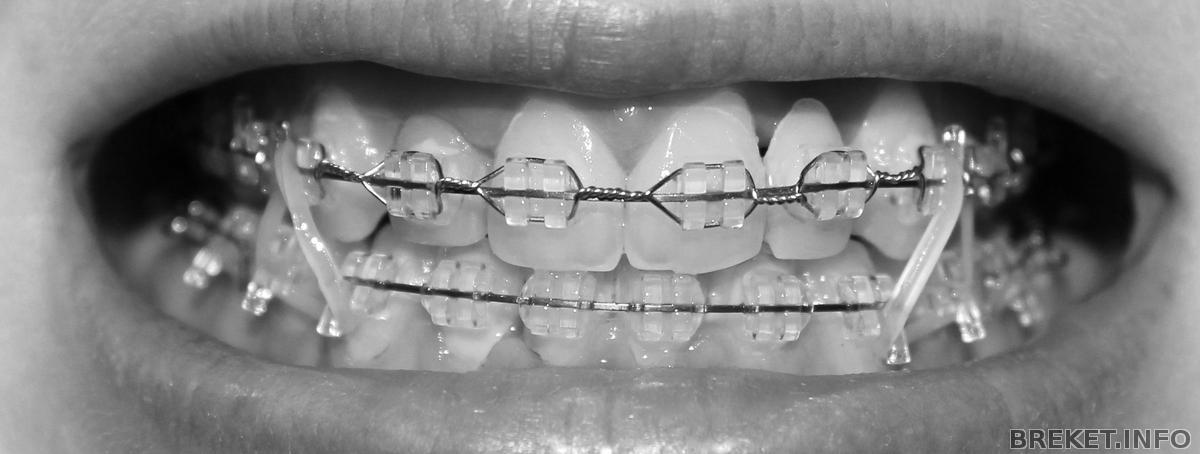

Дела обстоят так,за месяц до снятия, клык справа упирается, и упирается очень сильно, слева щель между челюстями давно закрыта. А тут до сих пор не до конца. Уже год хожу с тягами.

img_8267.jpg

Меся до снятия 2.

Так сейчас(вижу что низ с одной стороны выше, ибо гребаный клык сверху умудряется тянуть зубы к себе,а не опускаться сам,и с этим ничего не придумать:(); Читать далее »